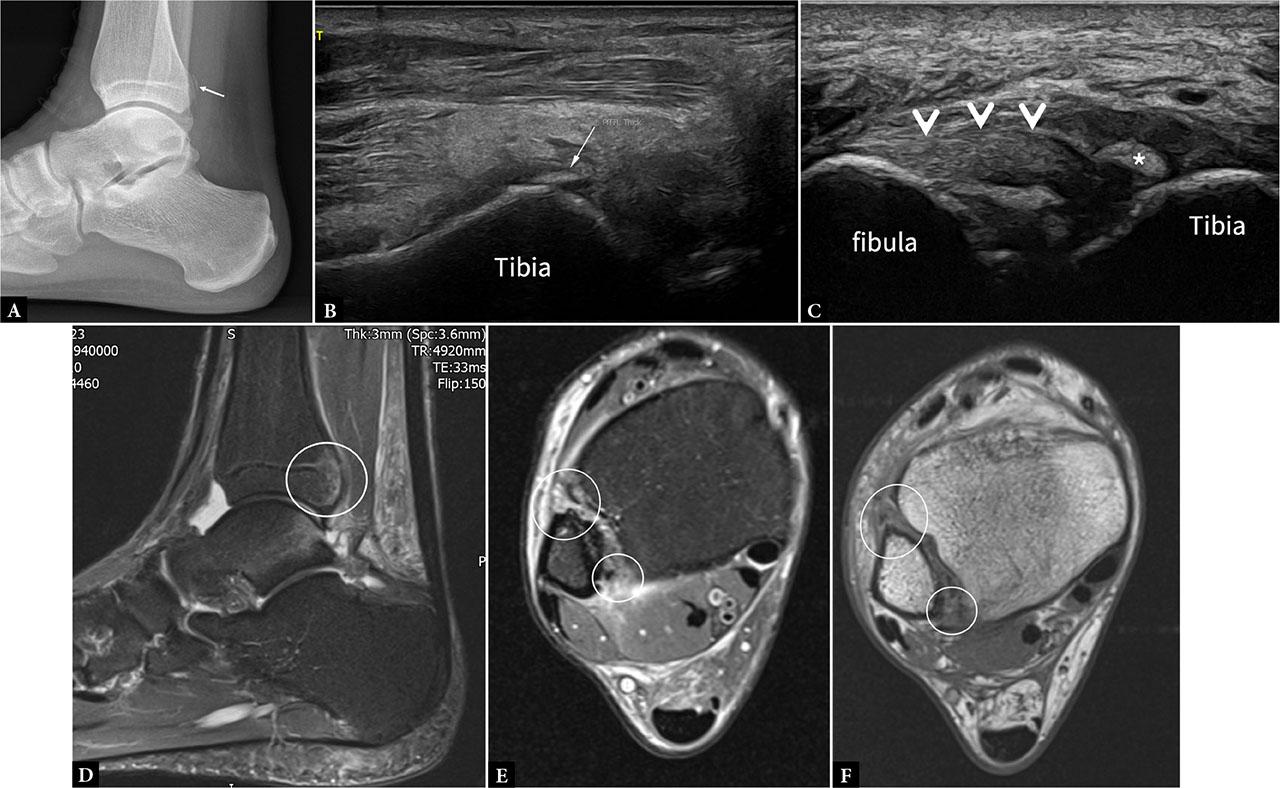

US and radiographic evaluation of a 22-year-old male soccer player with ankle twisting injury. Lateral view plain radiograph (A) shows a small avulsion fracture of the posterior aspect of the distal tibia (arrow). US long-section image (B) confirms the presence of the small avulsed bone fragment in the posterior aspect of the tibia. Axial oblique US image (C) shows thickened PiTFL (arrowheads) with discontinuity of the tibial attachment and the small, avulsed bone fragment (*). MRI sagittal proton density fat-saturated sequence (D) image shows mild bone marrow contusion in posterior aspect of the distal tibia. Axial proton density fat-saturated sequence (E) and T1W (F) show injury to both the AiTFL (large circle) and the PiTFL (small circle)

Ultrasound is more sensitive in demonstrating small avulsion fragments (Fig. 6, Fig. 7) or calcifications. In addition, dynamic assessment may help differentiate Grade II from Grade III injuries, with the amount of syndesmotic widening determining surgical versus conservative management(13).